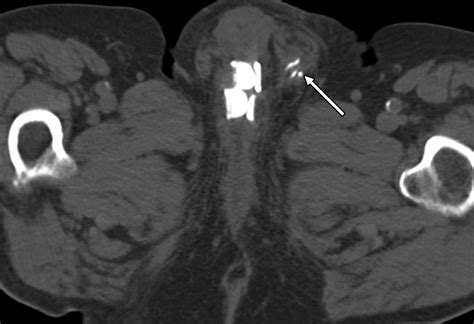

An Artificial Urethral Sphincter is a surgically implanted device designed to mimic the function of the natural sphincter muscle, which normally keeps the urethra closed to prevent urine leakage. When this natural muscle is damaged or weak, the AUS takes over the responsibility of controlling the flow of urine. The device is entirely contained within the body, making it discreet and effective for long-term use.

The system typically consists of three interconnected components:

• The Cuff: A circular balloon placed around the urethra that inflates to keep the urethra closed.

• The Pump: A small control mechanism placed in the scrotum (for men) or labia (for women) that allows the patient to manually deflate the cuff when they need to urinate.

• The Balloon (Pressure-Regulating Reservoir): A reservoir implanted in the abdomen that regulates the pressure within the system to ensure the cuff stays closed yet comfortable.

• artificial urethral sphincter radiology